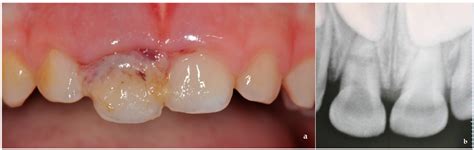

Root Fracture and Extrusive Luxation in Primary Teeth and Their ...